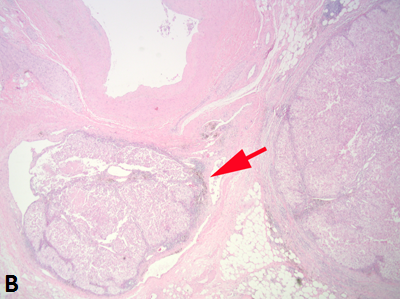

Figure 1B

Figure 1A. Rounded nodules in the renal sinus indicate sinus vascular involvement.

Sinus fat invasion occurs when intravenous tumor invades through the media (33), however, in some cases tumor bulging into the sinus can be difficult to interpret. Recommendations for sampling have varied with protocols ranging from sampling of the entire interface to 2-3 blocks (6, 7, 34, 35). At the meeting there was consensus that when invasion of the renal sinus is uncertain, at least three blocks of the interface should be taken. If invasion is grossly evident or obviously not present (small peripheral tumor) only 1 block is needed to confirm the gross impression.

Tumor grossly involving the renal vein is usually visible to the naked eye. A tumor thrombus typically expands the renal vein (Fig. 1B) and may or may not be adherent to the renal vein wall. If the surgical margin is clamped, there is a tendency for the renal vein margin to retract back from the tumor thrombus when the clamps are removed. There was near consensus that the actual margin and additional sections of the tumor thrombus should be sampled, particularly in areas where tumor is adherent to the wall.

Figure 1B. Tumor grossly involving the renal vein is usually visible to the naked eye. A tumor thrombus typically expands the renal vein. The renal vein margin (arrow) often retracts back from the tumor thrombus when vein clamps are removed.